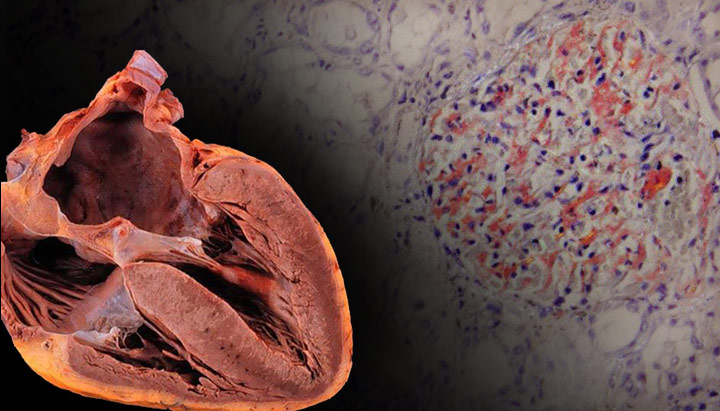

Дилатационная

Данная форма заболевания является наиболее распространенной. Ее главной характеристикой является значительное увеличение сердечных полостей, вызванное серьезной деформацией стенок. Со временем они теряют способность противостоять давлению, создаваемому поступающей кровью. Дилатационная кардиопатия протекает тяжело и быстро проявляется. У пациента наблюдается ухудшение состояния, а также сбои в работе сердца.

На начальных этапах болезни затрагивается одна из камер сердца. Наиболее неблагоприятные прогнозы связаны с дилатацией желудочков на ранних стадиях заболевания. Этот тип кардиопатии приводит к истончению стенок камер. Причины нарушений могут быть как приобретенными, так и врожденными. В первом случае к ним относятся:

Гипертрофическая

Деформация стенок желудочков является характерной особенностью данного состояния. Наиболее часто наблюдается поражение левой стороны сердца, однако утолщение может также затрагивать и правую его часть. При асимметричном изменении страдает межжелудочковая перегородка. Гипертрофическая кардиопатия приводит к аномальному развитию сердечной мышцы, в результате чего мышечные волокна располагаются в беспорядочном порядке.

Эта патология может быть как наследственной, так и приобретенной. Для ее отличия от аортального стеноза, гипертензии и коарктации аорты важно отметить отсутствие постнагрузки на миокард желудочков. При проведении эхокардиографии наличие систолических шумов указывает на обструктивный тип гипертрофической кардиомиопатии.

Данный тип дисфункции сердечной мышцы всегда имеет наследственный характер. При аритмогенной кардиомиопатии часть здоровых тканей заменяется соединительной или жировой тканью. Этот вид кардиомиопатии чаще всего передается по наследству, хотя в редких случаях может быть и приобретенным. Например, болезнь Наксоса относится к заболеваниям, которые передаются по рецессивному типу. На сегодняшний день аритмогенная кардиомиопатия изучена недостаточно, поэтому полное понимание ее этиологии остается затруднительным.